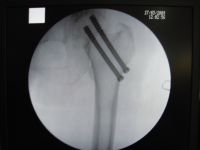

2.内固定:目前有条件的医院在电视X光机的配合下,采用闭合复位内固定,如无X光机设备,亦可采用开放复位内固定。在内固定术之前先行手法复位,证实骨折断端解剖复位后再行内固定术。内固定的形式很多,归纳约有以下几种类型:①Smith-Petersen三刃钉内固定:自1929年Smith-Petersen首次创用三刃钉以来,使股骨颈骨折的疗效显著提高,至今仍为常用的内固定方法之一。②滑动式内固定:现有各种不同式样的压缩钉或针。压缩钉或针可在套筒内滑动,当骨折线两侧有吸收时,钉向套筒内滑动缩短以保持骨折端密切接触,早期承重更利于骨折端的嵌插。③加压式内固定:此种内固定物带有压缩装置,能使骨折端互相嵌紧以利愈合。常用的有Charnley带有弹簧的压缩螺丝钉和Siffert使用的螺丝栓(Corkscrew Bolt)等。④多针(或钉)内固定:根据股骨上端骨结构和生物力学原则分别插入2~4根螺丝钉或钢钉,不但固定牢靠,而且可减少对股骨头的损伤。如Moore或Hagia针等。总之,内固定形式多种多样。

1.外固定:适用于外展型和中间型骨折,一般多采用患肢牵引或抗足外旋鞋8~12周,防止患肢外旋和内收,约需3~4个月愈合,极少发生不愈合或股骨头坏死。但骨折在早期有错位的可能,故有人主张以采用内固定为妥。至于石膏外固定已很少应用,仅限于较小的儿童。内固定适应证最广。对绝大部分内收型骨折均适用。一般约需4~6个月愈合,骨折愈合后仍应继续观察直至术后五年,便于早期发现股骨头缺血坏死。